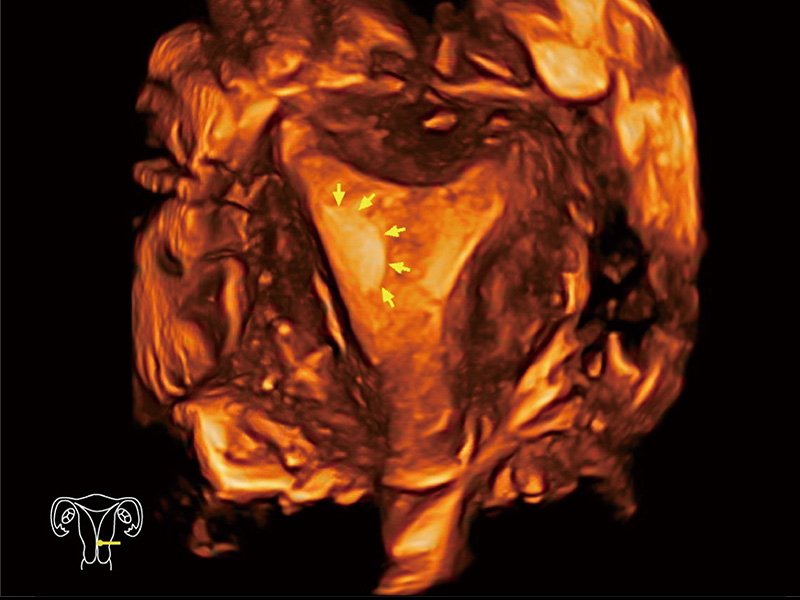

临床图

中央型宫腔粘连